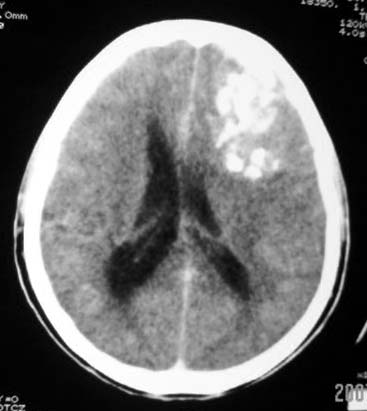

标题: CT7268:左额顶部病变增强片. [打印本页]

标题: CT7268:左额顶部病变增强片.

比较典型的少枝胶质细胞瘤ct表现,局部额骨垂直板有侵蚀变薄。

左额叶病灶内条片状高密度是钙化吗?是的话考虑少支胶质瘤可能大。不然有脑血畸形伴出血可能。

左侧额顶叶有条带状钙化的不规则形占位,增强呈不均匀轻度强化,局部颅骨受侵蚀变薄,典型的少支胶质细胞瘤。

比较典型的少枝胶质细胞瘤ct表现,局部额骨垂直板有侵蚀变薄